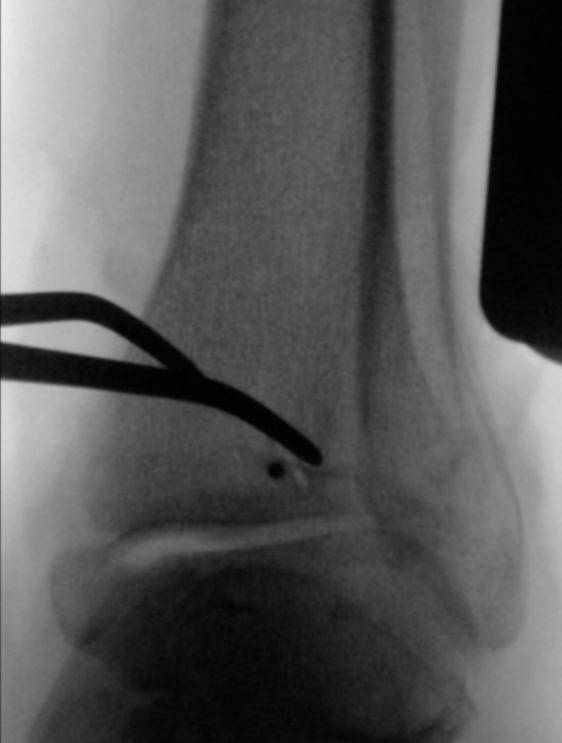

仔细行骨膜下剥离后,显露后踝骨折,清除嵌入的软组织,使用尖头复位钳进行解剖复位并临时固定(图3a)。确认复位满意后,于胫骨平台外侧三分之一、骨骺瘢痕近端确定导针进针点。此位置允许建立垂直于骨折平面的由后向前螺钉轨迹,从而在**化加压的同时避免关节内穿入。

经一长约1厘米的纵向皮肤切口,显露胫骨前侧皮质。在透视引导下,并使用两把小号Longbeck拉钩保护伸肌腱及神经血管结构,将一枚用于4.5毫米无头双螺纹加压螺钉的1.6毫米导针,从前内侧向后外侧、以约5-10°的向远端倾斜角置入(图3b–d)。经术中三维透视确认导针位置正确后(图3e),测量所需螺钉长度。

image.png

(a)

(b)

(c)

(d)

(e)

图3. (a–e): (a) 使用尖头复位钳临时固定;(b) 从前向后置入1.6毫米导针;(c) 踝穴位片,红线标记腓骨切迹后缘,蓝线标记前缘;(d) 点状末端视图证实轨迹位于切迹外;(e) 术中三维透视显示导针正确走行。